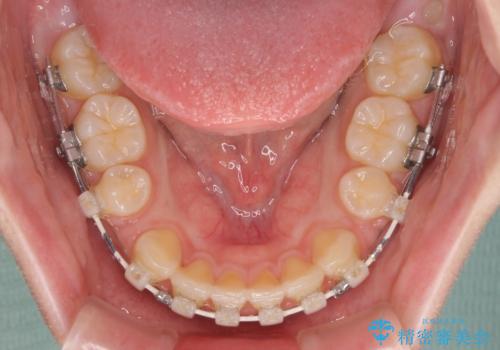

- 矯正装置

- 審美装置

- 2年6ヶ月

- 10-30回

- 出っ歯と口の閉じにくさ、デコボコを気にして来院された患者様です。

口元の突出感を改善するため、上下左右第一小臼歯4本の抜歯を行い、ワイヤー装置による矯正治療を行うこととしました。